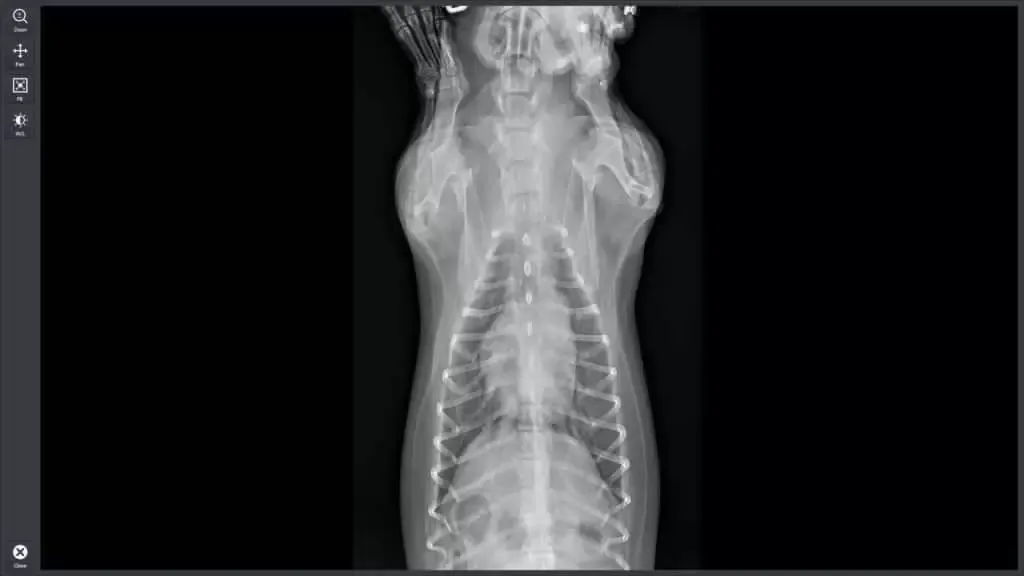

Przeswietlenie powinno być rozważane w sytuacjach, gdy lekarz weterynarii podejrzewa uraz, choroby kości lub inne schorzenia, które wymagają wizualizacji struktur wewnętrznych. Na przykład, jeśli zwierzę wykazuje objawy bólu lub dyskomfortu, RTG może pomóc w zdiagnozowaniu problemu. Warto również rozważyć przeswietlenie w przypadku podejrzenia nowotworów lub innych poważnych schorzeń, gdzie szybka diagnoza jest kluczowa dla wdrożenia odpowiedniego leczenia.